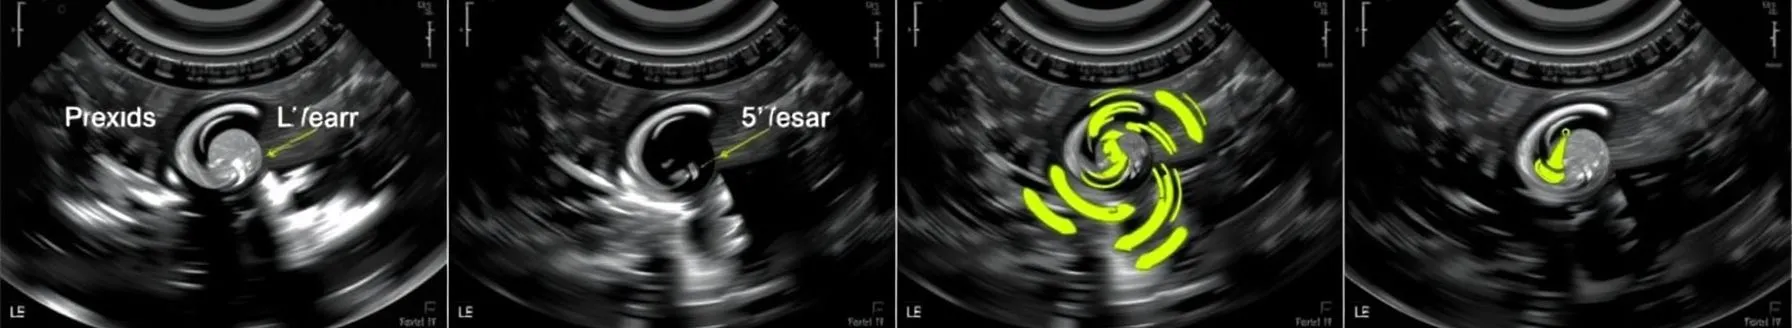

ECHO Evaluation of Stuck Valve

- The presentation outlines the utility of echocardiography (echo) in critical care, drawing a parallel between its development and the principles of sonar used in submarines. Echo, an ultrasound technique, is presented as a valuable tool for bedside assessment, particularly when physical examination is limited. Transducers, including phased array, convex, and linear probes, are essential tools.